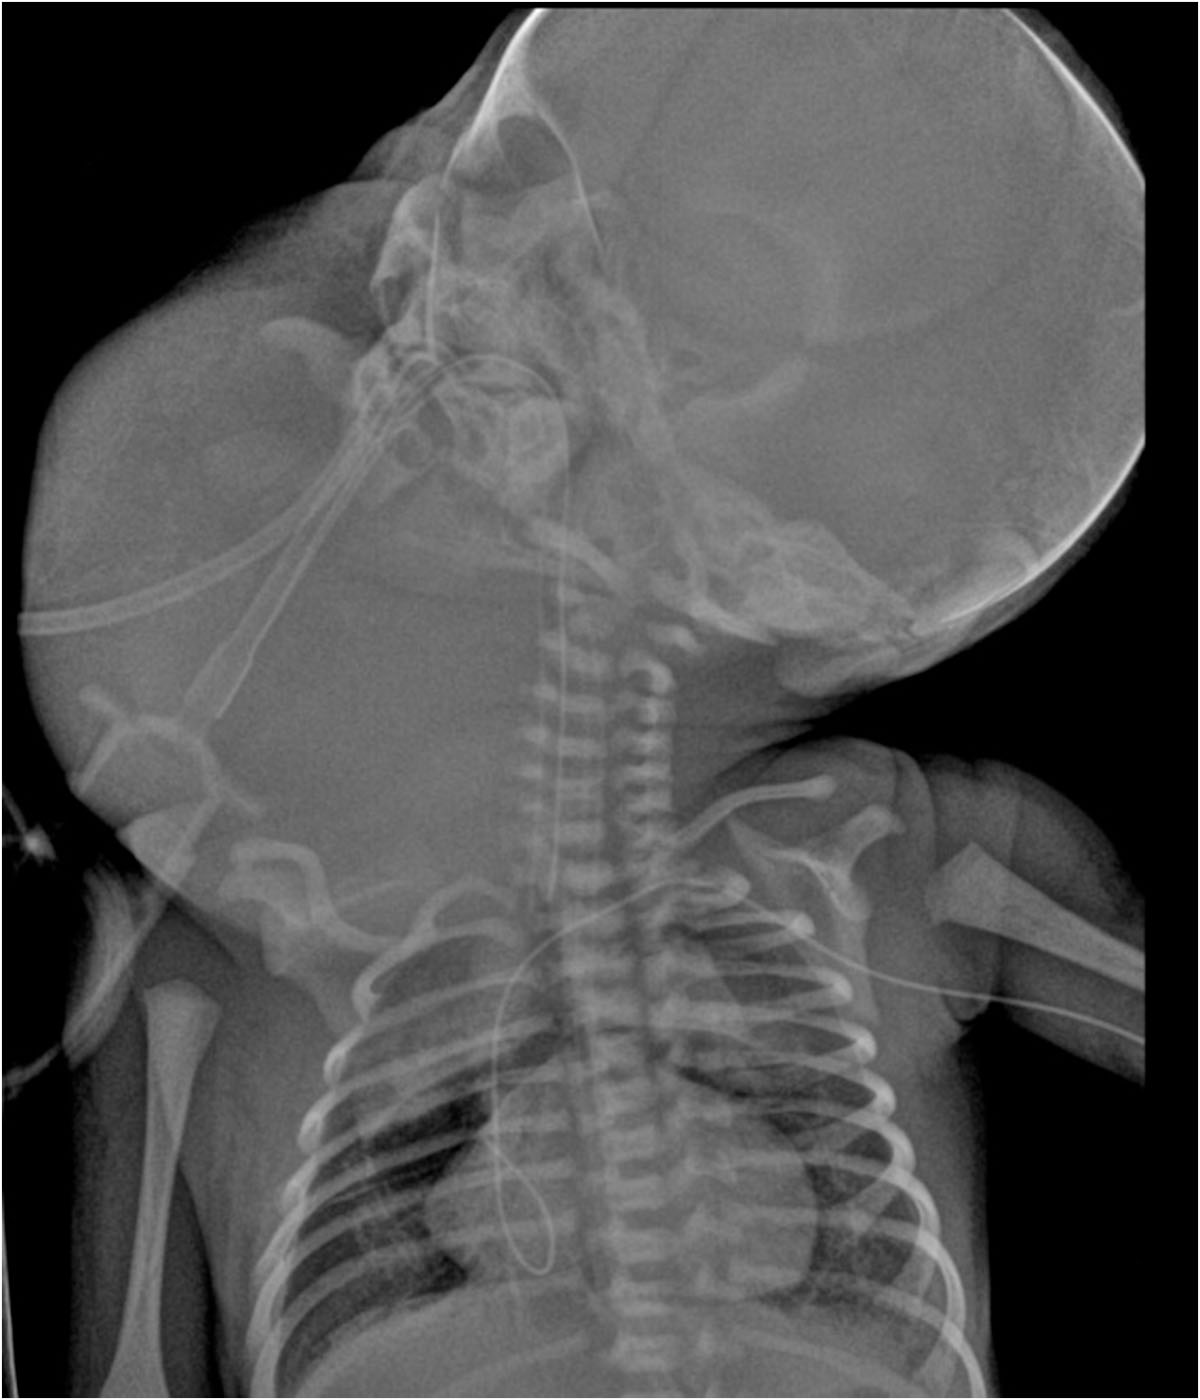

Paciente femenina recién nacido producto de primer gesta sin antecedentes heredofamiliares de relevancia con adecuado control prenatal; cuenta con antecedente patológico de amniodrenaje en la semana 34.4 por polihidramnios. Obtenida por vía abdominal, con manejo de vía aérea avanzada, por presentar tumoración en la región cervical derechade aproximadamente 12×8 cm, indurada, de bordes irregulares.

Se identifica imagen redondeada, de bordes lobulados, dependiente de tejidos blandos, heterogénea por áreas sólidas y quísticas internas, así como algunas calcificaciones irregulares dispersas, tras la aplicación de medio de contraste con realce ávido heterogéneo en sus porciones sólidas, con dimensiones de 89.3×88.3×80.9 mm y volumen de 333.6 cc; localizada en los espacios masticador, parotídeo, parafaríngeo, submandibular, visceral, supraesternal, perivertebral bucal y cervical posterior derechos.5. IMÁGENES

El teratoma cervical es una neoplasia congénita rara, derivada de células germinales pluripotenciales que contienen tejidos de las tres capas embrionarias. Representa menos del 5% de los teratomas pediátricos y su localización en el cuello puede ocasionar compromiso de la vía aérea, constituyendo una urgencia neonatal potencialmente mortal.

La tomografía computarizada (TC) muestra una masa compleja bien delimitada, con componentes sólidos, quísticos, calcificados y grasos, hallazgo característico de los teratomas maduros. La TC permite valorar la relación con estructuras vasculares, la vía aérea y el mediastino, siendo útil en la planificación quirúrgica.